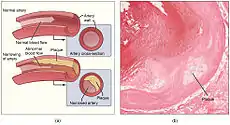

Coronary artery disease, also known as ischemic heart disease, is caused by atherosclerosis—a build-up of fatty material along the inner walls of the arteries. These fatty deposits known as atherosclerotic plaques narrow the coronary arteries, and if severe may reduce blood flow to the heart.[57] If a narrowing (or stenosis) is relatively minor then the patient may not experience any symptoms. Severe narrowings may cause chest pain (angina) or breathlessness during exercise or even at rest. The thin covering of an atherosclerotic plaque can rupture, exposing the fatty centre to the circulating blood. In this case a clot or thrombus can form, blocking the artery, and restricting blood flow to an area of heart muscle causing a myocardial infarction (a heart attack) or unstable angina.[58] In the worst case this may cause cardiac arrest, a sudden and utter loss of output from the heart.[59] Obesity, high blood pressure, uncontrolled diabetes, smoking and high cholesterol can all increase the risk of developing atherosclerosis and coronary artery disease.[55][57]